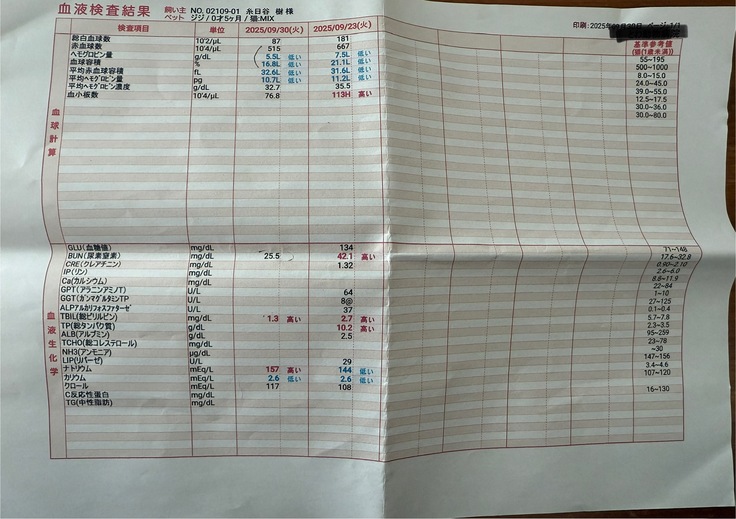

黄疸で血液や目は真っ黄色。

腹水でお腹はパンパンになっていて、エコー検査で腎臓まで腹水が流れてしまっていることがわかりました。

すぐに血液検査など詳しい検査をしていただき、出た結果です。

タンパク質からの計算式に基づいて、この時点でおそらくFIPで間違いないだろうとの診断でした。

検査をし、ありがたいことに検査結果は良好で腎臓や黄疸の値もものすごく下がっていました。

驚くことに結果はとっても良好で、全ての値がほぼ正常値まで戻っていました。

9/23時点で1.4キロだった体重は1.56キロまで増えてくれていました。